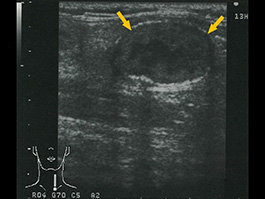

甲状腺左葉横断像。境界不整な低エコー結節(矢印)を認める。小型ではあるが、境界・内部エコーなどは典型像と類似している。 |